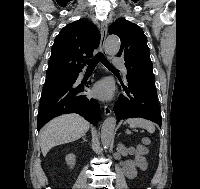

CT画像の例

頚部CT水平断 胸部CT冠状断(縦隔条件) 胸部CT冠状断(肺野条件)